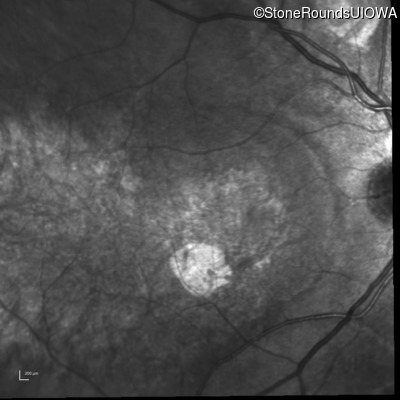

Infrared Fundus Photograph - Right - 20/100

Exemplar